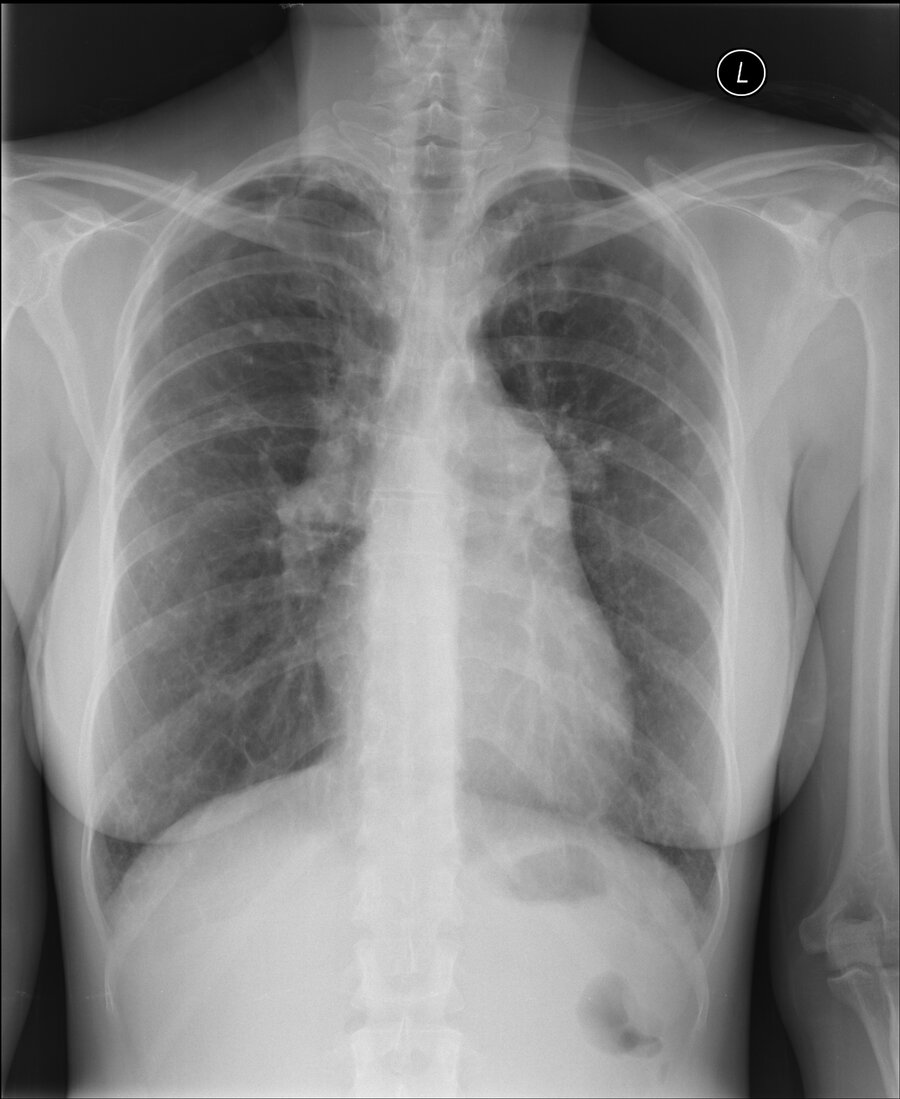

Chest radiograph is shown.

Which of the following is the most likely abnormality seen on this frontal chest radiograph?

Hilar adenopathy

Interstitial lung disease

Mediastinal mass

Prominence of the pulmonary arteries